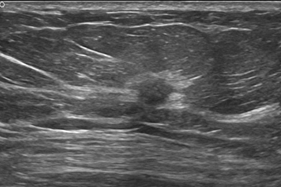

ABUS独特的冠状面成像VS常规超声

ABUS容积探头VS常规超声探头